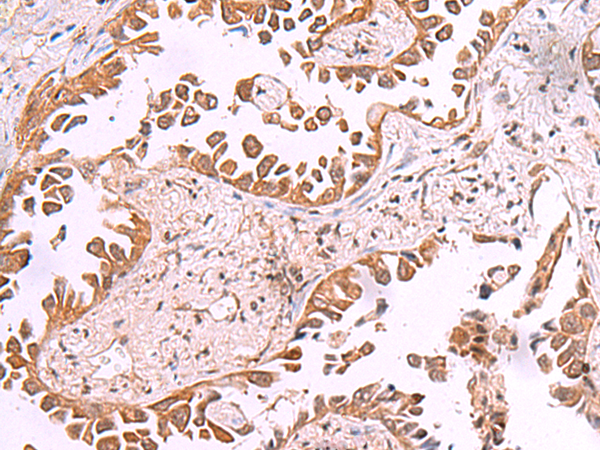

The image is immunohistochemistry of paraffin-embedded Human lung cancer tissue using (AK9 Antibody) at dilution 1/85. (Original magnification: ×200)

The image is immunohistochemistry of paraffin-embedded Human esophagus cancer tissue using (AK9 Antibody) at dilution 1/85. (Original magnification: ×200)